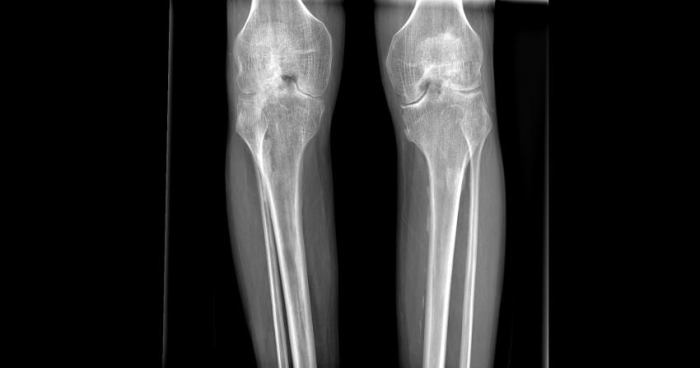

患者术前双膝情况